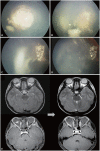

Figures